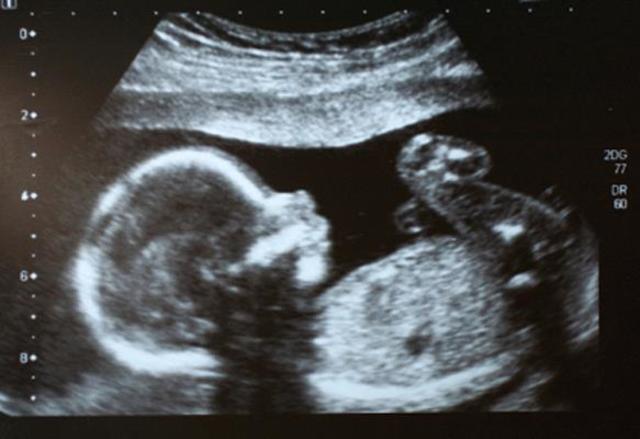

En el 4 mes, mamá tiene control, el médico le dice que va bien el bebé, que casi no se deja ver, pero que todo está normal, que va creciendo sano.

Mamá recibe una gran sorpresa, papá va a visitarla de sorpresa en su día de descanso, quiere saber cómo va todo. Mamá le cuenta que ya tiene 5 meses, que a un no sabe que es ya que casi no se deja ver, pero que va creciendo sana y fuerte.

Mamá sale de el trabajo a su control habitual, está emocionada porque llegó el día en que sabrá si es niña o niño. El doctor le informa que todo va bien que es una niña que va creciendo poco a poco.